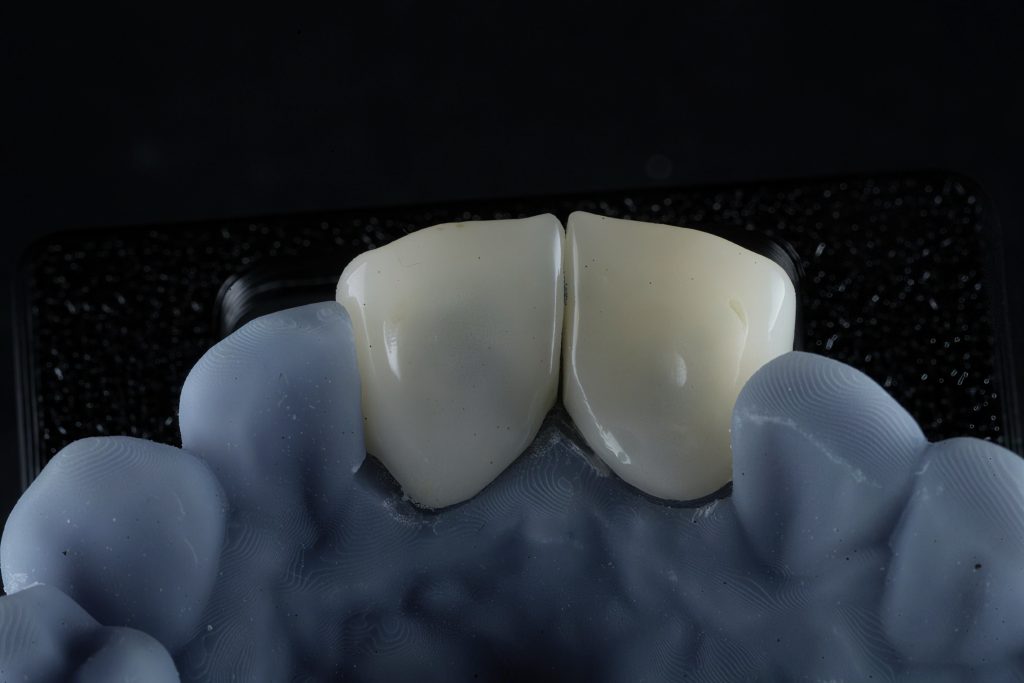

Step 2 — Digital Smile Design & Exocad Workflow

A full digital workflow was used:

- Intraoral scanning

- DSD-based analysis for ideal tooth proportions

- Exocad 3D designing of width/height ratio, incisal embrasures, line angles

- 3D printed mock-up for physical evaluation

This allowed previewing the final aesthetic and functional outcome before touching the tooth.

Final Outcome

- Natural shape and symmetry restored

- Improved occlusion and anterior guidance

- Stable gingival profile

- Lifelong color stability and strength from Emax

- Patient reported instant aesthetic and functional improvement